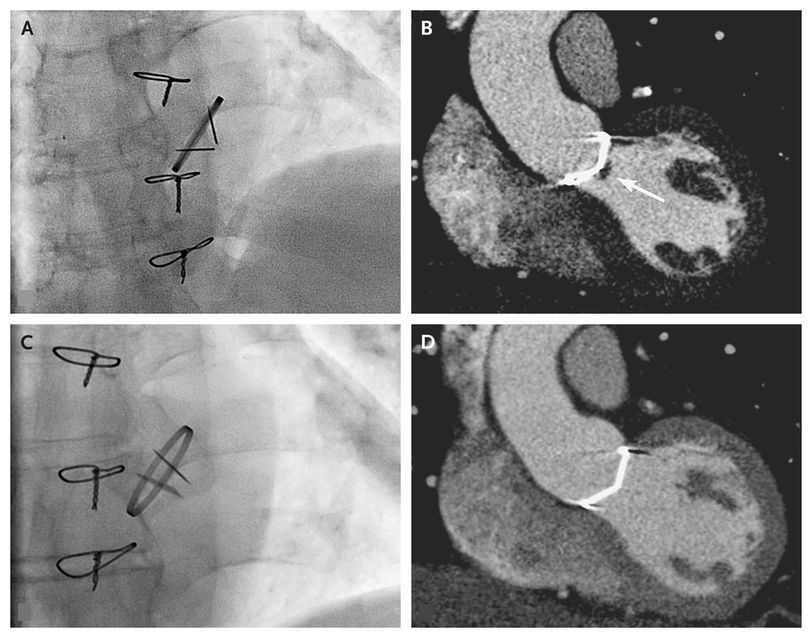

A 63-year-old man with a bileaflet mechanical aortic-valve replacement presented with a 3-week history of no audible leaflet clicks. Since he had undergone valve placement 6 years earlier for endocarditis, the clicks had always been clearly audible. The physical examination revealed a new systolic murmur and confirmed the absence of leaflet clicks. Transthoracic echocardiography showed a severely increased peak gradient (75 mm Hg, as compared with 32 mm Hg at baseline) over the mechanical aortic valve, and diminished opening of both leaflets was detected on fluoroscopy (Panel A). Cardiac computed tomographic angiography (CTA) revealed a hypodense mass on the leaflets that was suggestive of thrombus, although a vegetation could not be ruled out (Panel B, arrow; and video 1). Target values for the international normalized ratio were increased from 3.0 to 4.0, and aspirin was administered. The patient was scheduled to undergo repeat aortic-valve replacement in 12 weeks. However, when he was subsequently admitted for surgery, he reported hearing the leaflet clicks again. The patient reported having had no symptoms of embolic events during this period. Transthoracic echocardiography showed normalization of the pressure gradient, and fluoroscopy showed normal opening of both leaflets (Panel C), which was suggestive of thrombus resolution, as confirmed on CTA (Panel D, and video 2). These images illustrate that the absence of clicks from a prosthetic heart valve requires urgent evaluation.